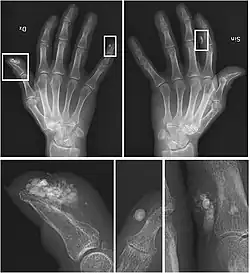

| CREST syndrome (calcinosis and sclerodactyly) | |

CREST causes thickening and tightening of the skin with deposition of calcific nodules ("calcinosis").